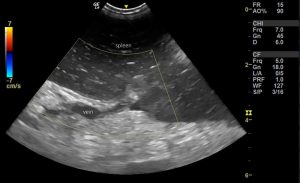

On sonography the spleen exhibits the classic ‘starry sky’ parenchymal pattern which is typical although not specific for torsion:

There is no detectable flow in the splenic vessels with Doppler.

At the point where the splenic veins cross the capsule there are hyperechoic triangles of mesosplenic fat (arrowheads):